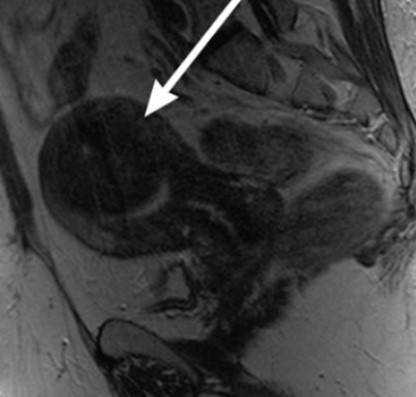

МРТ матки выполняют по показаниям в сложных диагностических случаях не ранее 4 месяца гестации. Дифференциальную диагностику миомы проводят с аденомиозом, раком и саркомой матки, полипами эндометрия, опухолями яичников, забрюшинными новообразованиями, трофобластической болезнью. При необходимости беременной назначают консультации уролога, онколога, хирурга.

- МРТ малого таза. Отражает точную топографию, размер и количество миоматозных узлов. Часто шеечная опухоль сочетается с миомами тела матки. Данные исследования используются при выборе тактики лечения.

Миомы в области матки составляют особую угрозу в ходе процесса вынашивания ребенка. Так, лейомиома может получить быстрый рост во время беременность в связи с изменением гормонально фона (повышение уровня эстрогенов в организме женщины). Миома шейки матки иногда приводит к нарушению кровоснабжения стенки. Миома в нижнем маточном сегменте повышает риск кровотечения и сложности выполнения кесаревого сечения. Миомная опухоль, расположенная за плацентой, может спровоцировать недостаточность и отслойку плаценты. Миомные образования в ходе беременности обычно выявляют с помощью УЗИ. МРТ здесь играет уточняющую роль, когда нужно дифференцировать миому с объемными образованиями яичников и уточнить источник болевого синдрома при геморрагической дегенерации узла.

Признаки миомы на МРТ

Диагностировать миому на МРТ не составляет особого труда. Врачи на томографических изображениях видят её в виде четко очерченного образования округлой формы. На магнитно-резонансных снимка определяется псевдокапсула миомы в виде тонкого ободка, гиперинтенсивного по Т2. По МР картине специалист может говорить о характере миомы, является ли она кистозной или миксоидной, лейомиомой или липолейомиомой. В зависимости от неоднородности миомы будут видны сопутствующие процессы - кровоизлияние, некроз, обызвествление.

Подслизистая миома матки (указана стрелкой)

Субсерозная миома на МР-сканировании

При магнитно-резонансной томографии получают множественные снимки анатомической зоны во фронтальной, сагиттальной и аксиальной плоскостях. Врач имеет возможность изучить каждый участок органа, выявить малейшие отклонения от нормы. Миоматозные узлы обычно выглядят на МР-сканах как округлые гипоинтенсивные образования разных размеров. Смена режимов позволяет выявить псевдокапсулу, оценить характер кровоснабжения опухолей.